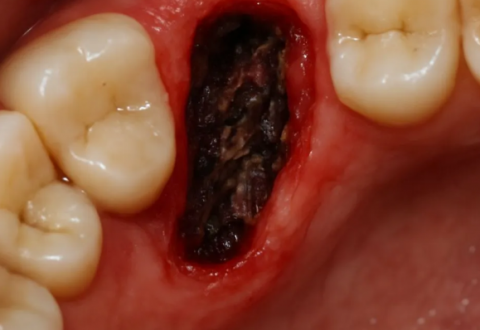

He had developed alveolar osteitis, commonly known as a dry socket. This painful complication occurs when the protective blood clot that forms in the tooth socket after an extraction is dislodged or dissolves prematurely. This exposes the underlying bone and nerve endings to air, food, and fluids, causing intense pain and delaying healing. It’s a condition often directly linked to patient behavior in the critical first 72 hours post-surgery.

Humiliated and in excruciating pain, William called the oral surgeon’s emergency line. In the stark exam room, his neglect was evident. The surgeon confirmed a dry socket. The treatment was uncomfortable but transformative:

Gentle Irrigation: The socket was gently flushed to remove food debris.

Medicated Dressing: A special, sedative-packed dressing was placed inside the socket to shield the exposed bone, provide direct pain relief, and promote healing.